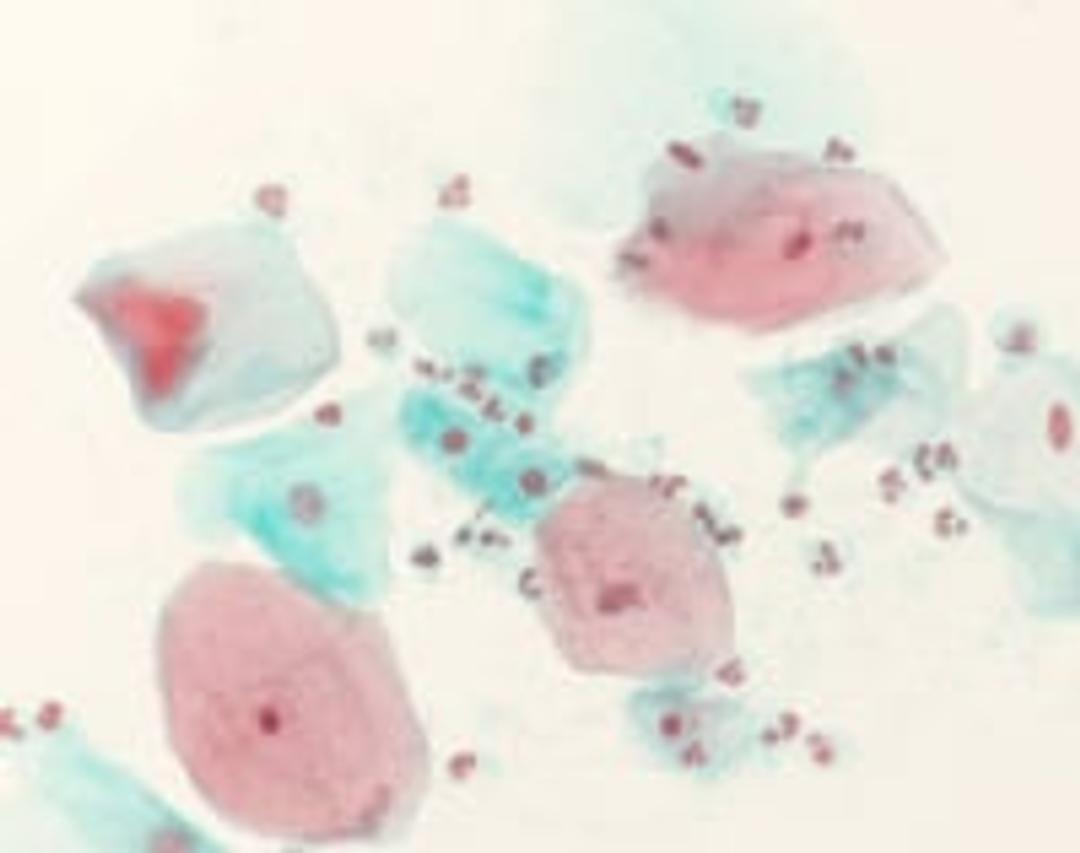

Shorr staining solution

Cytological Staining Reagents

During the course of menstrual cycle, the sex hormones cause characteristic changes in the vaginal epithelium. The hormone situation can be evaluated with the aid of stained vaginal smears. The Shorr staining is used for hormonal cytodiagnosis only, however the differences between eosinophilia and cyanophilia are more distinct. The ratio of eosinophilic to cyanophilic cells casts light on the effects of the follicular and the corpus luteum hormones. The number of eosinophilic cells increases under the influence of the follicular hormone, whilst that of the cyanophilic cells increases under the influence of corpus luteum hormone. The Shorr staining solution is an IVD registered product and CE certified, thus can be used for clinical diagnostic purposes.